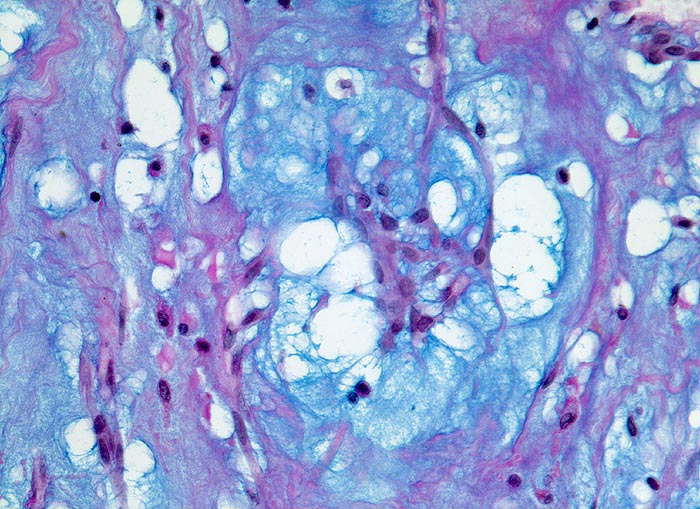

AP/ Vorhofmyxom

Vorhofmyxom

Herz Vorhof